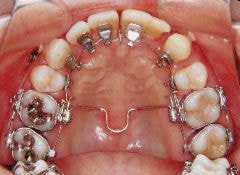

治療例2 (補綴処置+矯正)